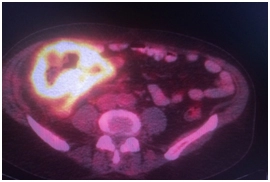

Выполнено ПЭТ/КТ исследование с 18F-ФДГ.

Выявлен гиперметаболический опухолевый процесс в области слепой и восходящей ободочной кишки (SUVmax 21,9), окружающая параколитическая клетчатка неравномерно инфильтрирована, с небольшим количеством жидкостного содержимого. Просвет кишки неравномерно сужен. В окружающей параколитической клетчатке, брыжейке тонкой кишки, отмечаются лимфоузлы,  размерами до 6-8 мм по КО, с умеренным накоплением РФП, SUVmax 4,3.

IMG_4389-27-09-18-09-40.JPG IMG_4389-27-09-18-09-40.JPG IMG_4389-27-09-18-09-40.JPG IMG_4389-27-09-18-09-40.JPG